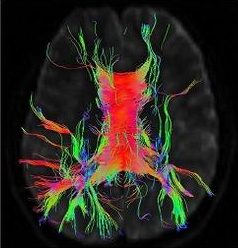

研究の結果、エ〇チな動画をたくさん見た人は脳の刺激中枢部分が委縮した脳をしています。

研究者たちは「エ〇チな動画をたくさん見た人の場合、脳の領域の中で刺激と報酬反応を司る線条体が委縮していることが確認できた」という衝撃的な結果を伝えました。